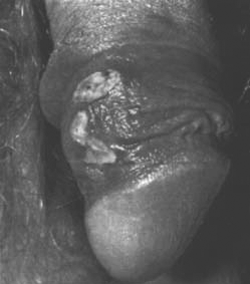

1.5 Verruche genitali (Condylomata acuminata)

Infezione

virale con formazione di neoplasmi di vulva, prepuzio, glande.

Terapia:

- Trattamento dal ginecologo/urologo anche

dei partner sessuali.

- „Complementare¾.

ã>

ric. E1), E2) (L¼efficacia, senza altri rimedi, non Ë garantita).

Oltre

a possibili infezioni (p.es. herpes genitalis, candida albicans, condyloma) il

pi˜ importante disturbo strutturale Ë la fimosi: il prepuzio non si lascia

ritirare dietro il glande (fimosi incompleta: solo in stato di erezione).

Complicazioni:

La

fimosi promuove lo sviluppo di carcinoma del pene; si ipotizza che lo smegma,

secrezioni del glande sia la causa.

Circoncisione:

ectomia parziale o completa del prepuzio; usata anche per motivi rituali o

preventivi (Stati Uniti profilassi dei neonati).